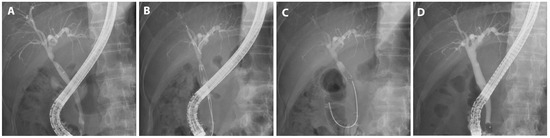

A patient subjected to hemi-hepatectomy developed a hilar stricture that was treated using FCSEMS; additionally, a plastic stent was prophylactically deployed in another bile duct to prevent cholangitis (Figure 4).

Figure 4.

FCSEMS treatment of biliary anastomotic stricture after liver resection. A case diagnosed with biliary anastomotic stricture after left hemihepatectomy for liver donation and treated with FCSEMSs is presented. (A) Magnetic resonance cholangiopancreatography shows segmental narrowing at the hilar and common hepatic duct with mild central intrahepatic bile duct dilatation, and a 2 cm-sized biloma was observed at the resection margin. (B) A hilar stricture was observed on cholangiogram. (C) An FCSEMS (6 mm in diameter, 5 cm in length; KAFFES) was deployed at the site of biliary anastomotic stenosis, with a plastic stent placed prophylactically, as expansion of the FCSEMS could narrow the adjacent branches. (D) After the FCSEMS was in use for 6 months, including one replacement, the stent was removed, and the procedure was terminated after confirming that the biliary anastomotic stricture was resolved.